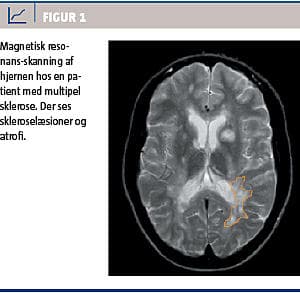

I fire af studierne anvendtes magnetisk resonans-skanning som sygdomsmarkør [2-5], men forskellige effektmål og forskellige skanningstidspunkter begrænsede analysen, hvorfor signifikante subgruppeanalyser bør tolkes med forsigtighed (Figur 1).